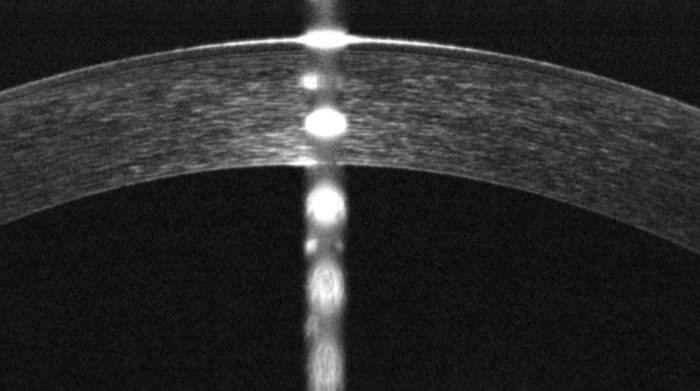

Ortoqueratología y control de la miopia. Qvision en Eurok iberica 2016.

Ortoqueratología. Rangos de aplicación

Ortoqueratología. Una alternativa a la sequedad en usuarios de lentes de contacto